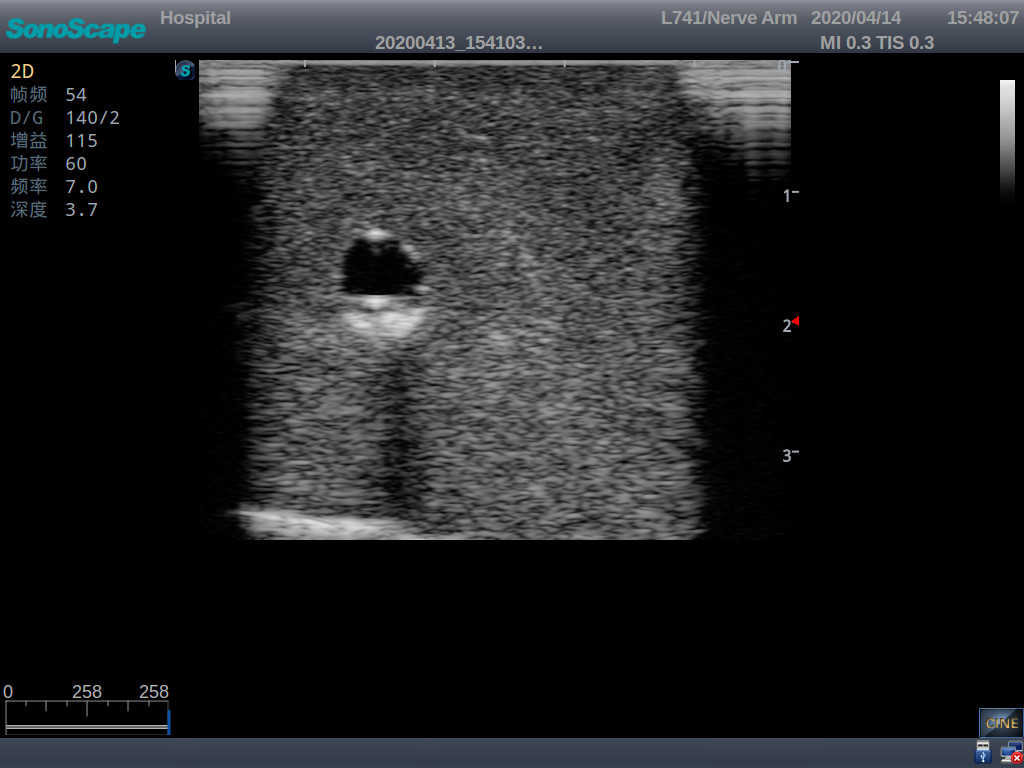

Model TYE1510.1

Outline

It is a model covering up from lobulus auriculae plane to the umbilical plane, and it has anatomical structures like clavicle, rib, sternocleidomastoid, jugular vein and basilic vein.

Skills Gained

· PICC training

· Trocar puncture

· Skin dilation with the expander

· Insert the catheter into the central vein along the guide wire

Features

1)   Made of high molecular polymer ultrasound material, close to the real skin

2)   It can be used by real ultrasound machines

3)   Clear and real images of the tissues and organs (basilic vein and superior vena cava)

4)   When conducting vascular puncture, the piercing can be truly felt, and venous blood outflow can be seen

5)   Observe the guide wire marches

6)   Detect whether the catheter is properly placed

7)   Modules of the puncture position are replaceable